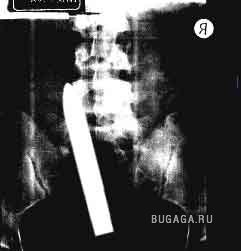

Ни для кого теперь уже не секрет, что у людей есть жопы. У каждого она своя и у всех разные. Жопы бывают человеческие и другие, большие и маленькие, плоские и выпуклые, висячие и упругие, в общем, всякие. А еще жопы бывают сытые и голодные. У кого сытая попа, тот её холит и лелеет, она вся такая ранимая и нежная. А у кого голодная жопа, тот её пичкает всем, что попадётся под руку, может затолкать туда всё, что угодно. Такую жопу ничто не берёт. Ни слово, ни дело, ни заноза, ни пуля, ни штык, ни добрый подсрачник! Прозвали их люди чудо-жопы! Чудо-жопы имеет не каждый, а только тот, кто регулярно упражняется в скармливании жопе различных инородных предметов. Этих ректальных сластолюбцев люди тоже кое-как прозвали, но мы не будем отвлекаться, с нас достаточно знать факт, что люди имеют жопы. Кто воспламенел желанием поэкспериментировать, но не знает, что именно засунуть в недра своего драгоценного проголодавшегося зверя, предлагаю посмотреть варианты. Ну а кому просто интересно, тот глазеет на серию снимков, сделанных медиками в разное время и в разных странах, но в одинаково патологичных случаях. Можно также прочитать пару случаев кормления, и чем это закончилось. Кого картинки могут задеть за живое, не принимайте близко к… живому :):):)

Список вещей, извлеченных из чудо-жоп:)

Список вещей, извлеченных из чудо-жоп:)